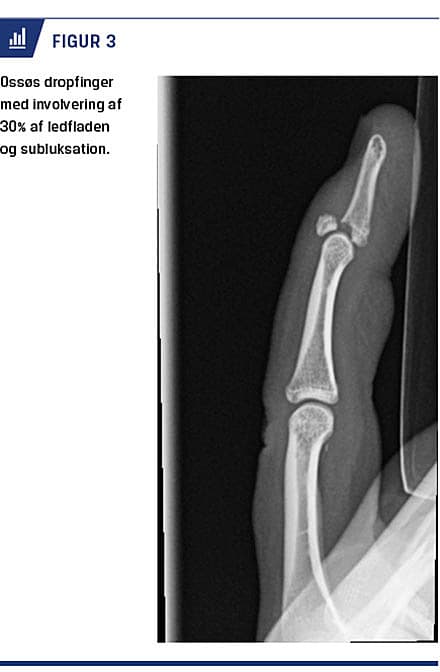

DROPFINGER

Formålet med behandlingen af dropfinger er at genoprette den aktive ekstension i DIP-leddet. Der er ikke konsensus om behandlingsmodalitet og -længde [26]. De fleste forfattere anbefaler dog operativ behandling ved åbne læsioner, involvering af mere end en tredjedel af ledfladen (Figur 3), subluksation, ledinkongruens og svigt af ikkeoperativ behandling [27]. Ved skinnebehandling holdes DIP-leddet kontinuerligt ekstenderet i en neutral stilling i seks uger, mens PIP-leddet er frit bevægeligt [27]. Behandlingen gentages, hvis DIP-leddet flekteres inden for seks uger, og der opstår reruptur eller refraktur [27]. Nogle forfattere anbefaler intermitterende immobilisering med efterfølgende brug af natskinne. 40% af de skinnebehandlede har imidlertid en persisterende strækkedefekt på 5-10 grader i DIP-leddet, mens 70% af patienterne har hudproblemer

Ikkedisplacerede, stabile frakturer og ossøs dropfinger med involvering af mindre end en tredjedel af ledfladen og uden subluksation kan behandles på en skadestuen. Intraartikulære frakturer, frakturluksationer i PIP-leddet, svært komminute og åbne frakturer (inkl. Seymour-fraktur), såvel som subkapitale frakturer og kondylfrakturer hos børn bør konfereres med eller henvises til håndkirurgisk vurdering. Tidlig mobilisering skal altid tilstræbes.